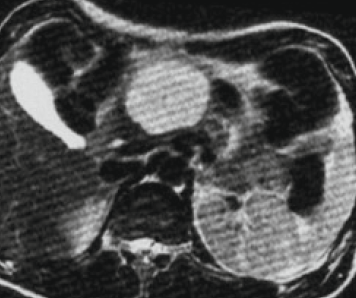

Low field

Mid field

High field

#whyCMR 🧲